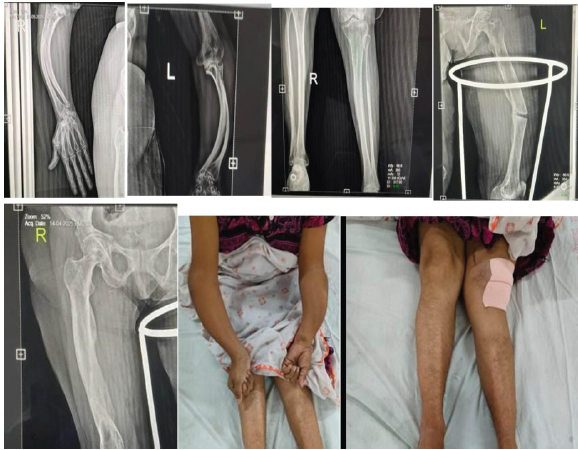

A 34-year-old female with known type ⅠA OI was admitted to our emergency department for a spontaneous left midshaft femur fracture on weight-bearing. She had a history of an atypical left femur fracture 1 month back, for which she was managed conservatively on oral medications. She also reported that she had a right femur fracture at 18 months of age while massaging, then had B/L upper limb forearm fractures while playing at around 8–10 years, all managed conservatively. The patient is of short stature with 1.30 m (Figs. 1 and 2).

Figure 2: Pre-operative X-rays and clinical photos of the upper limb and lower limbs.

On presentation, the patient was conscious, oriented, and hemodynamically stable, with complaints of pain and swelling in her left femur. The diagnostic workup revealed a midshaft left femur fracture with bowing deformity. Bony deformities are present in almost every long bone.